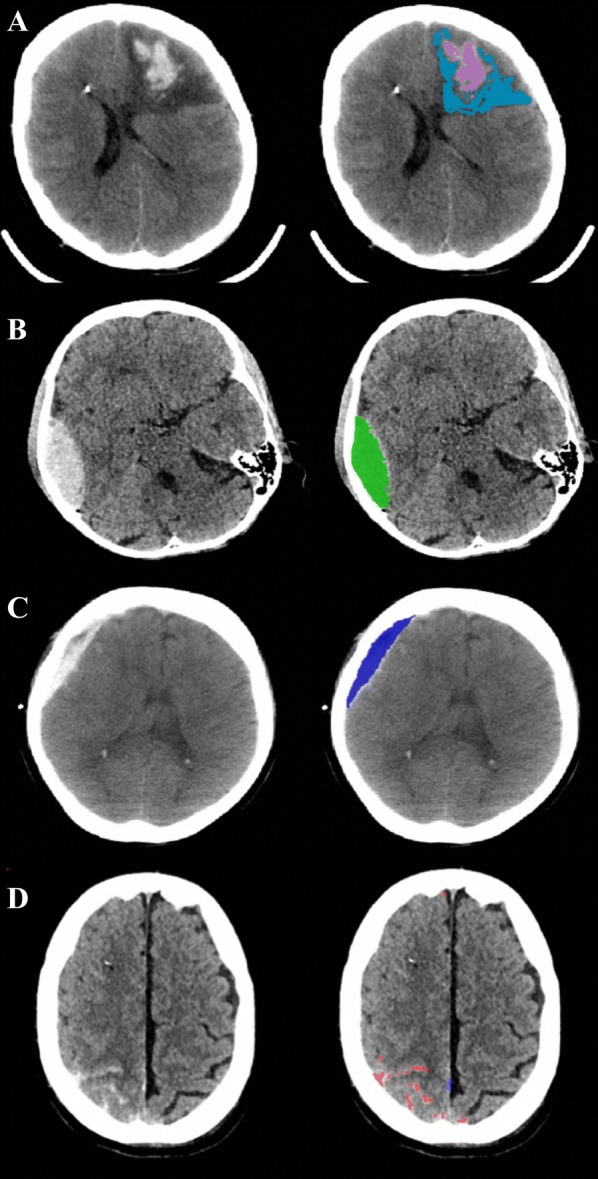

Methods: We conducted a retrospective cohort analysis on 50 TBI patients who had undergone high-frequency multimodal intracranial monitoring and for which at least two brain computed tomography (CT) scans had been performed in the acute phase of injury. We first performed univariate analyses on the full cohort to identify non-neurophysiological factors (i.e., initial lesion volume, timing of scan, coagulopathy) associated with traumatic lesion growth in this population. In a subset analysis of 23 patients who had intracranial recording data covering the period between the initial and repeat CT scan, we then correlated changes in serial volumetric lesion measurements with cerebrovascular reactivity metrics derived from the pressure reactivity index (PRx), pulse amplitude index (PAx), and RAC (correlation coefficient between the pulse amplitude of intracranial pressure and cerebral perfusion pressure). Using multivariate methods, these results were subsequently adjusted for the non-neurophysiological confounders identified in the univariate analyses.

Results: We observed significant positive linear associations between the degree of cerebrovascular reactivity impairment and progression of pericontusional edema. The strongest correlations were observed between edema progression and the following indices of cerebrovascular reactivity between sequential scans: % time PRx > 0.25 (r = 0.69, p = 0.002) and % time PAx > 0.25 (r = 0.64, p = 0.006). These associations remained significant after adjusting for initial lesion volume and mean cerebral perfusion pressure. In contrast, progression of the hemorrhagic core and extra-axial hemorrhage volume did not appear to be strongly influenced by autoregulatory status.